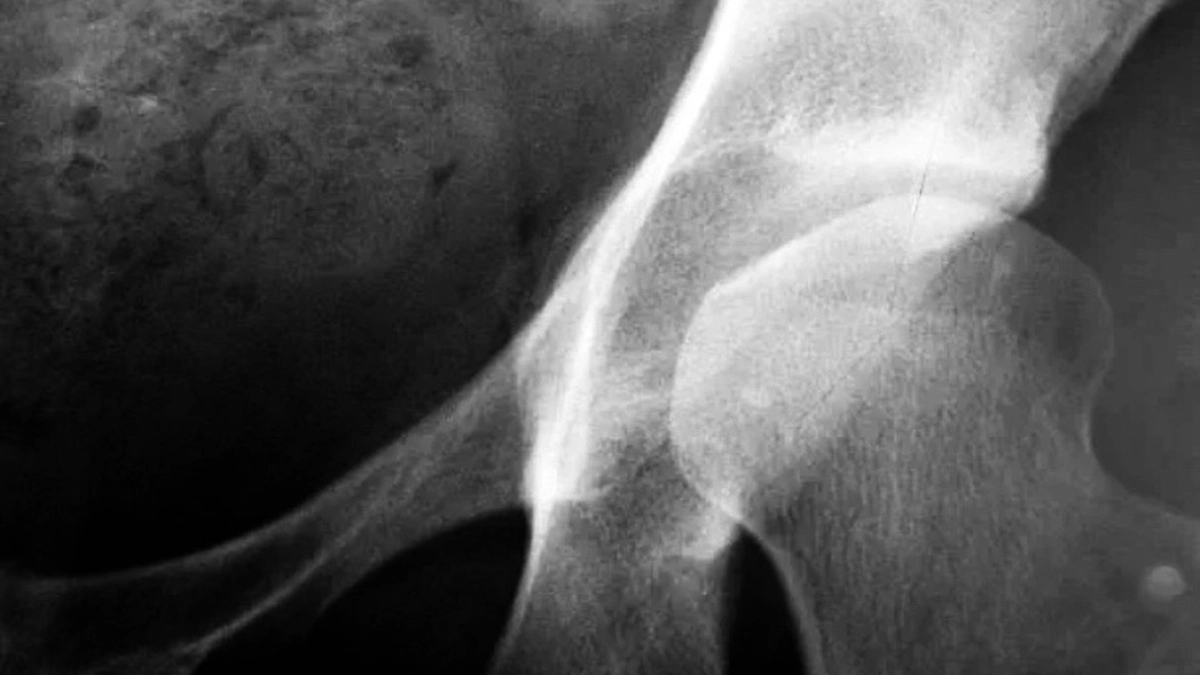

Kemik yoğunluğu ölçümü diğer adıyla kemik dansitometri, kemik yapısındaki minerallerin yoğunluğu ölçer. Mineral ve kemik yoğunluğu kaybını değerlendirmek için kullanılır. Bu ölçüm yapılırken özel bir x ışını kullanılır mineral ne kadar fazlaysa kemik yoğunluğu o kadar fazla çıkmaktadır. Yoğunluğun fazla olması demek kemiklerin daha güçlü ve kırılmaya karşı daha dayanıklı olması anlamına gelmektedir. Bu ölçüm kişi yaşlandıkça kemik rahatsızlıklarını tespit etmenin bir diğer yoludur. çok düşük seviyelerde x ışını kullanılır. Çift enerjili x ışını apsorsiyometrisi anlamına gelir. kemik taramasında oldukça kullanılan tıbbi bir yöntemdir.

Kemik dansitometri, zamanla kemiklerde bulunan minerallerin, kolajen liflerinin azalmasıyla başlayan kemik rahatsızlıklarının tespitinde kullanılır. 40 ve üzeri yaşlarda kemik erimesi riski daha yüksektir. Bu yüzden kişilerin her iki yılda bir kemik yoğunluğu ölçümü yaptırması uzmanlar tarafından önerilir. Kemik dansitometri osteropoz riski olup olmadığını belirlemede de kullanılır, osteropoz kemiklerin zayıflaması ve kırılma durumudur. Bu ölçüm özellikle omurga ve kalça kırıklarının riskini değerlendirir. Menopoz sonrası kadınlar hormonal değişiklikler nedeniyle osteropoz riski taşımaktadırlar. Bu yüzden özellikle menopoz dönemindeki kadınların ölçümlerini aksatmadan yaptırmaları önerilir.